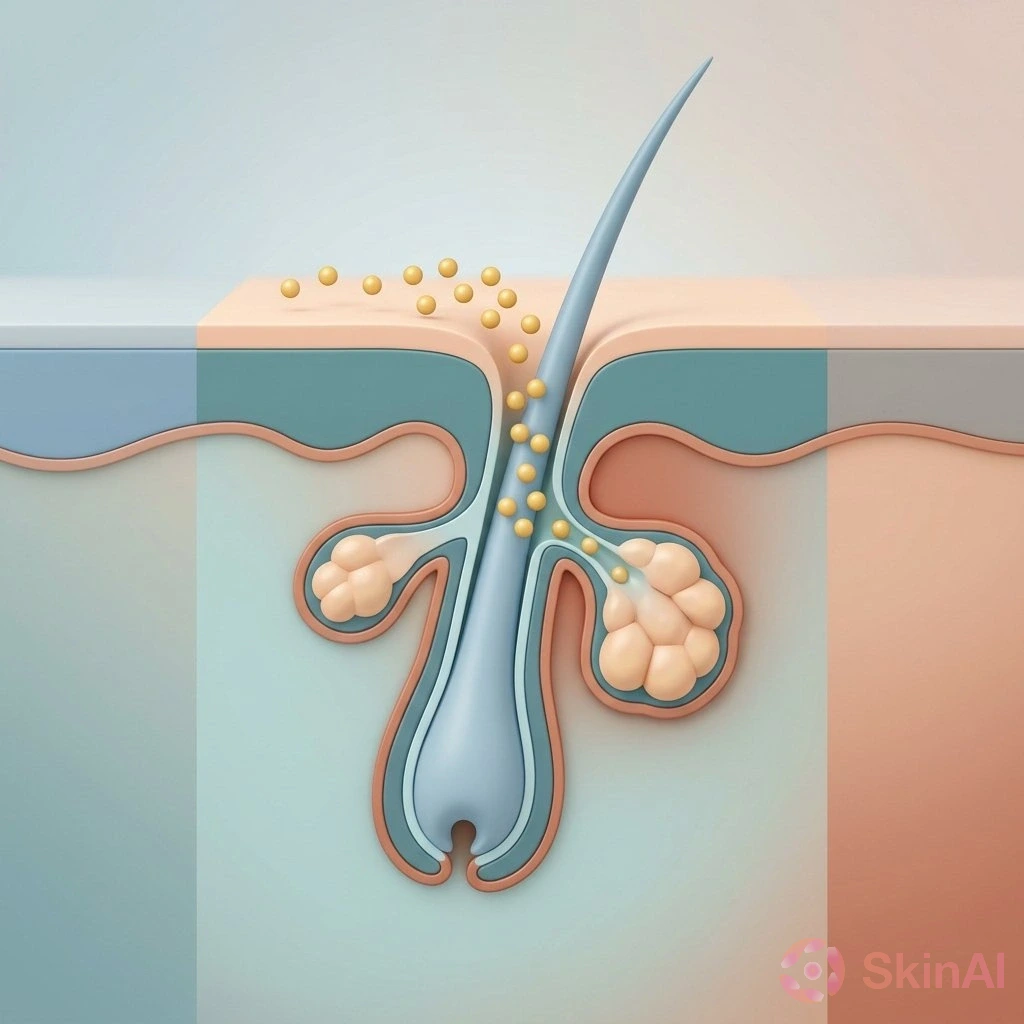

Malassezia Folliculitis vs Acne: How to Spot and Treat the Difference

Discover how to tell Malassezia folliculitis from acne and learn the best treatments for each to clear your skin effectively...